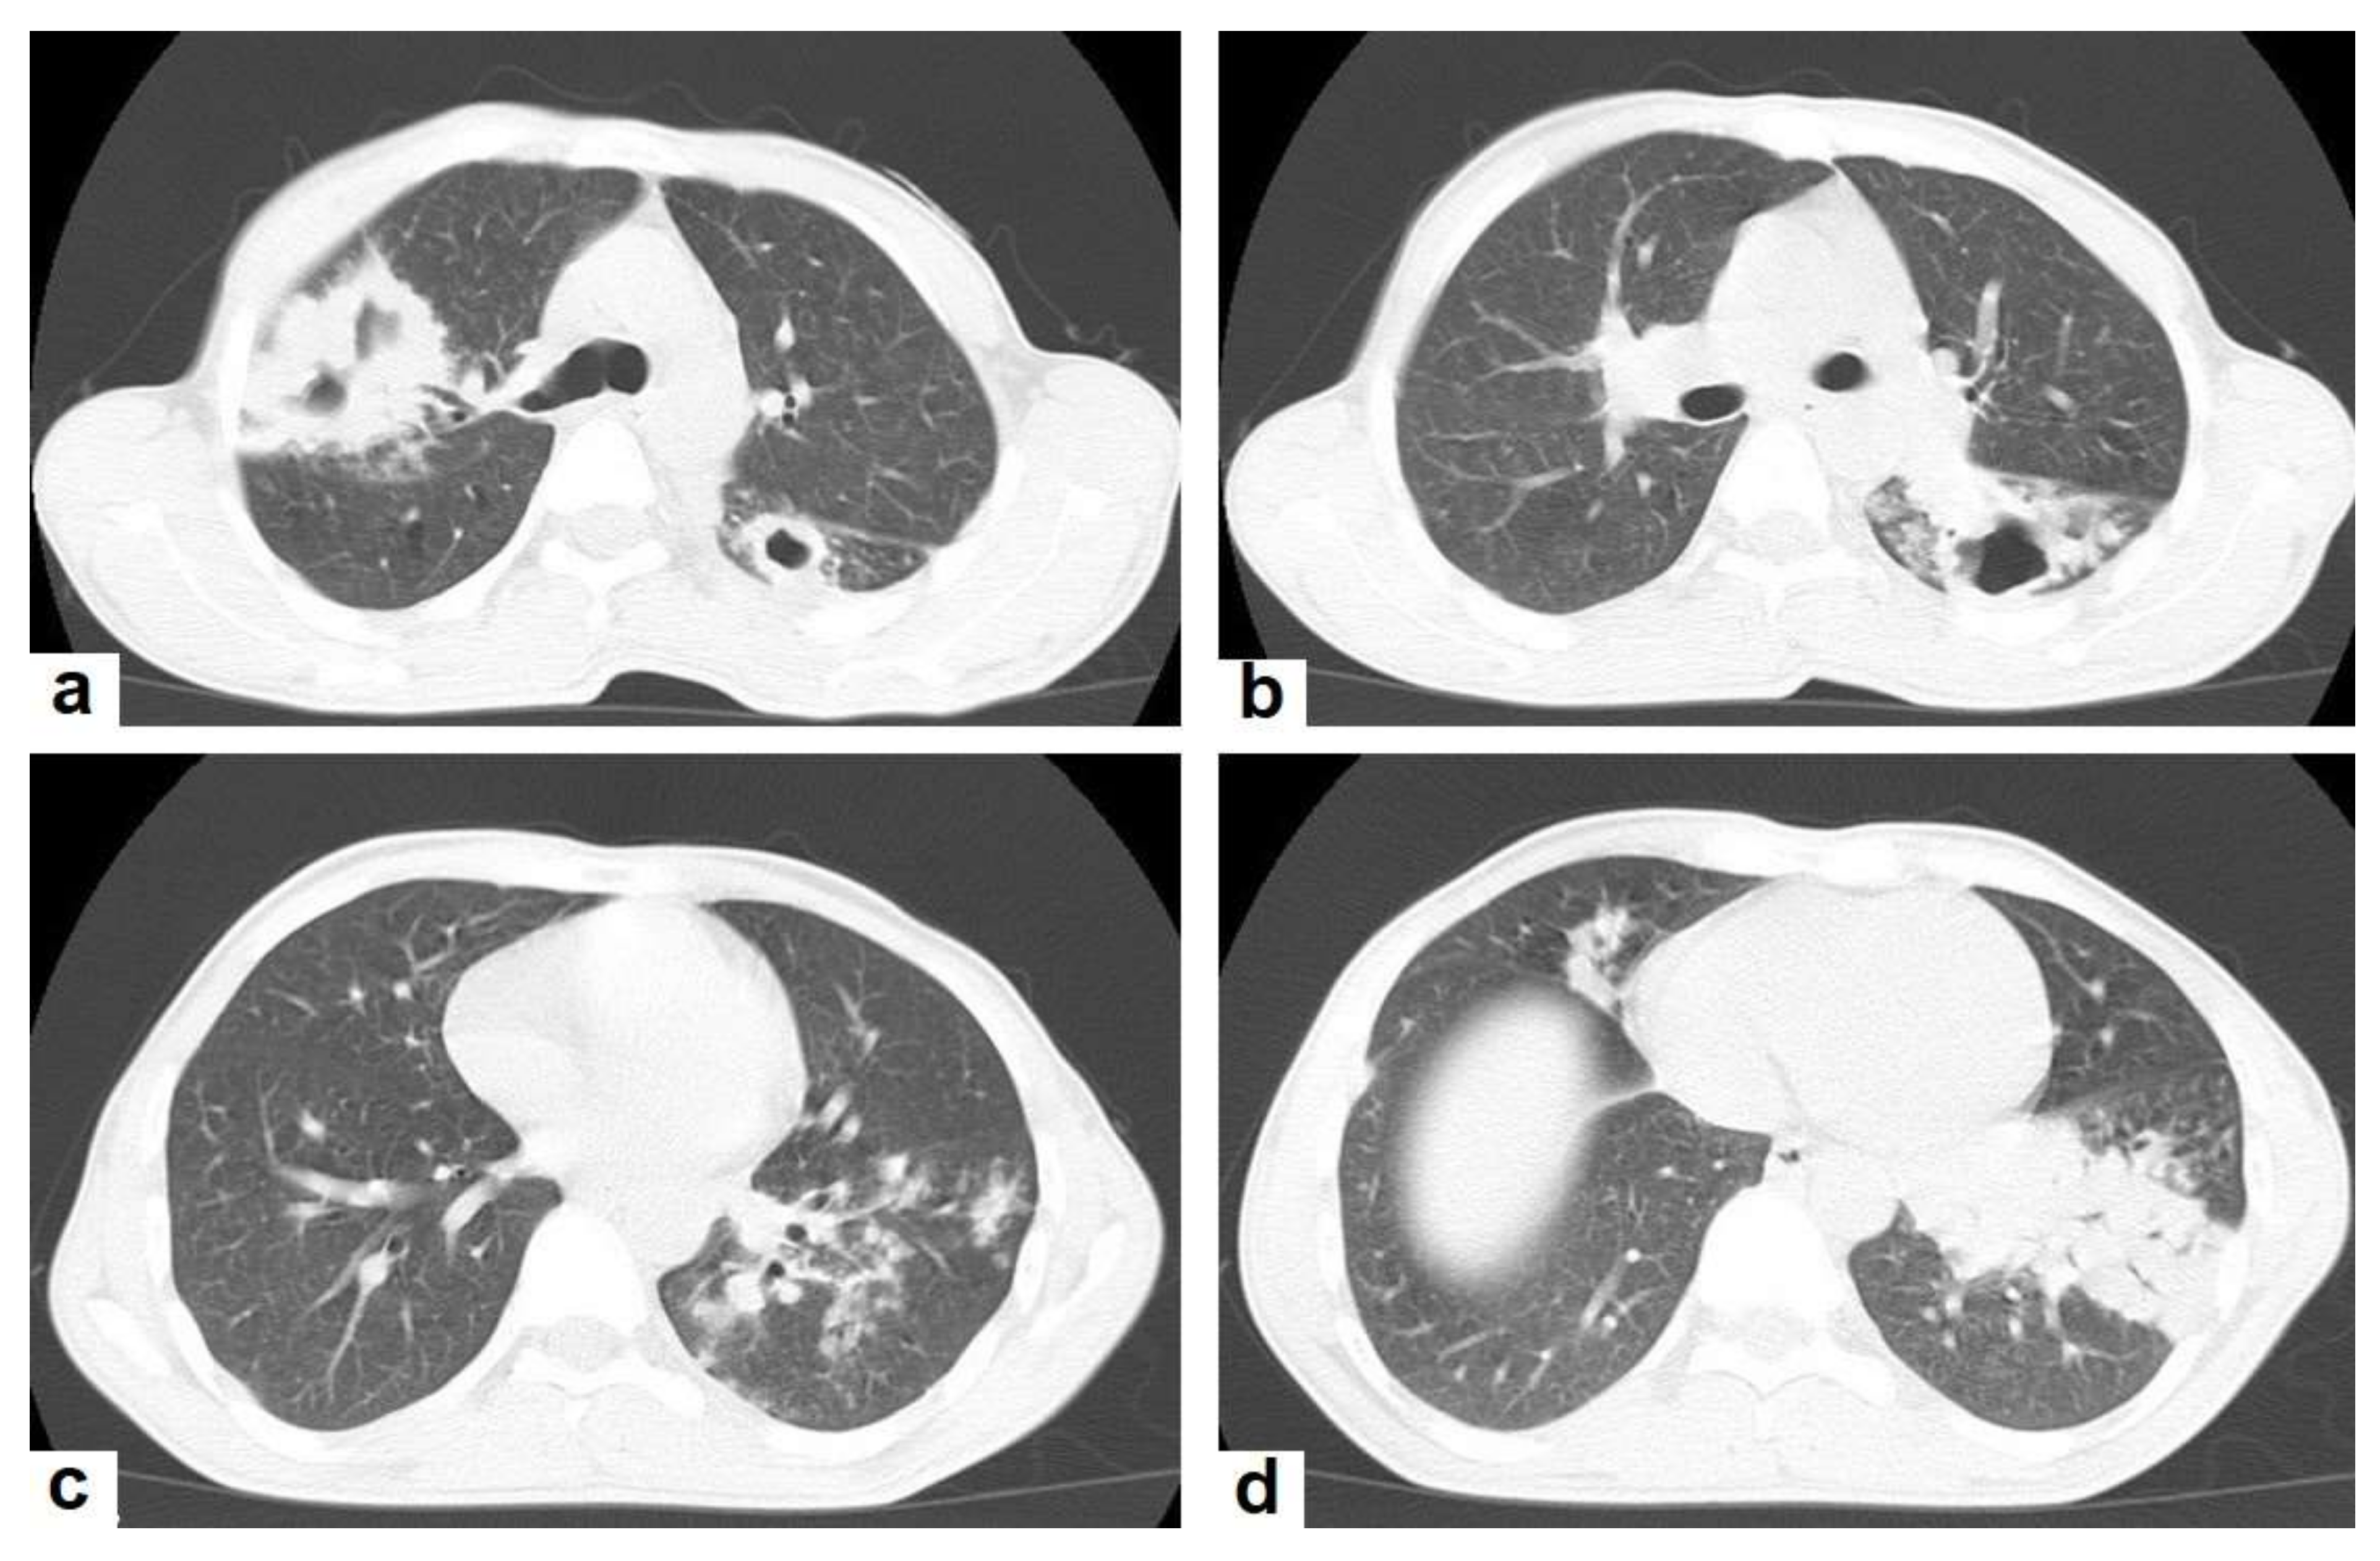

Figure 3. Post primary TB in a 45-year-old male with cough and hemoptysis. Axial images of chest CT show (a) cavitary lesions in the right upper lobe and upper segment of the left lower lobe surrounded with consolidation, (b) cavitary lesion in the upper segment of the left lower lobe with thick irregular wall surrounded by patchy ground glass opacities, (c) centrilobular nodules and tree-in-bud nodules, and (d) consolidation in the left lower lobe with air-bronchograms.

• Consolidation (Figure 3) is considered to be one of the most common features of postprimary TB, which is usually focal, patchy heterogeneous, or poorly defined. It involves the apical and posterior segments of the upper lobes and the upper segments of the lower lobes [10]. Consolidation with ipsilateral enlarged hilar or paratracheal LNs could strongly suggest TB. CT is better able to detect small and subtle TB consolidations, which are usually peribronchial or subpleural and involve multiple lung segments [13].

• Cavitation (Figure 3 and Figure 4) is a common finding in postprimary TB, and it is characterized as being several centimeters in size with thick irregular walls. Cavities are often seen within consolidation and may persist after treatment predisposing to a bacterial or fungal superinfection or adjacent vascular erosion causing hemoptysis [1,10]. In postprimary TB, both consolidation and cavitation have a predilection for the apical and posterior segments of the upper lobes and the upper segments of the lower lobes [1,14]. This predilection of TB is attributed to the relative over-ventilation, high oxygen tension, and delayed lymphatic clearance in these regions [16]. Thick wall cavities are an important differential diagnosis of a pulmonary abscess, septic emboli, aspergilloma, granulomatosis with polyangitis (Wegener’s granulomatosis), lung malignancy, and others [17].

• Centrilobular nodules (Figure 4 and Figure 5) occur due to the communication of active TB with the bronchial tree resulting in endobronchial spread. It occurs in most cases of active TB. It appears as centrilobular nodules and a tree-in-bud sign on CT images [1,10]. The tree-in-bud pattern is seen on high-resolution CT images as 2–4 mm centrilobular nodules of soft tissue density that are connected to multiple branching linear structures of the similar caliber, arising from a single stalk. It commonly occurs in the endobronchial spread of TB and is highly suggestive of active TB. However, a tree-in-bud is a CT manifestation of the diverse entities of lung diseases, including TB, cytomegalovirus, respiratory syncytial virus, obliterative bronchiolitis, diffuse panbronchiolitis, cystic fibrosis, airway-invasive aspergillosis, allergic bronchopulmonary aspergillosis, and pulmonary metastasis [18].